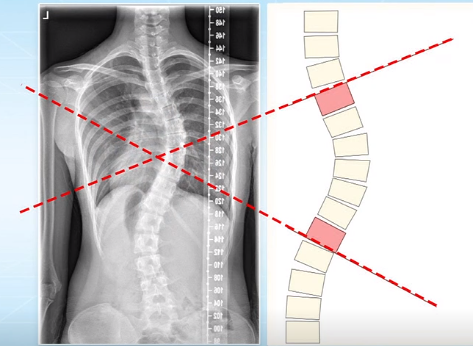

脊柱側(cè)彎的角度測(cè)量